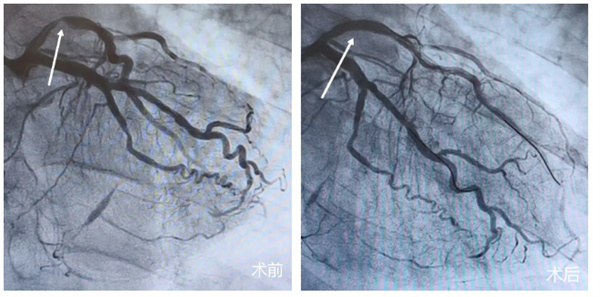

心血管三科赵福海主任医师、张大武主任医师迅速接棒。冠脉造影显示:患者左前降支(LAD)近段狭窄95%。迅速开通 “罪犯血管”,血管前向血流恢复至正常,患者胸痛症状明显缓解,生命体征趋于平稳。